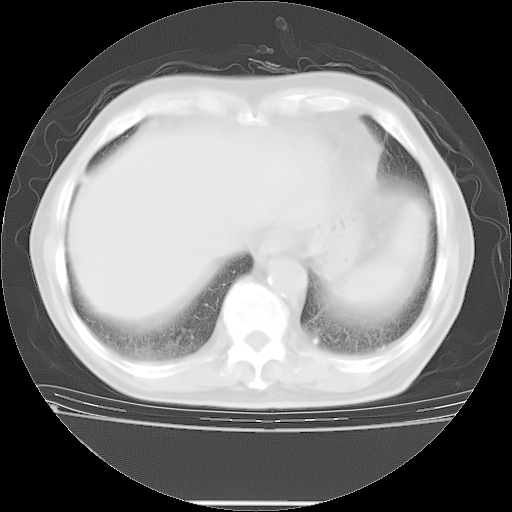

今天复查肺部CT,发现双肺广泛磨玻璃样改变。所以我把3月19日和5月9日相隔50天的肺部CT上传。请大家会诊。

5月9日肺部CT(在4月27日齐鲁医院肺部CT描述部分肺组织磨玻璃样改变,12天后肺组织广泛磨玻璃样改变)

大致读了系列胸部CT:纵隔窗无明显异常,肺窗:从4、27至今:主要是双肺中下野外带可见毛玻璃样改变,目前处于急性肺泡炎阶段,至于原因考虑1、结替组织或胶原血管性疾病所致?2、恶性疾病如恶组在肺部所致的表现或细支气管肺泡癌?3、药物或其它原因如肺蛋白沉着症所致肺泡炎目前不太可能?总之,明天就去请我院的呼吸科、感染科、血液科和临免专家会诊哈。